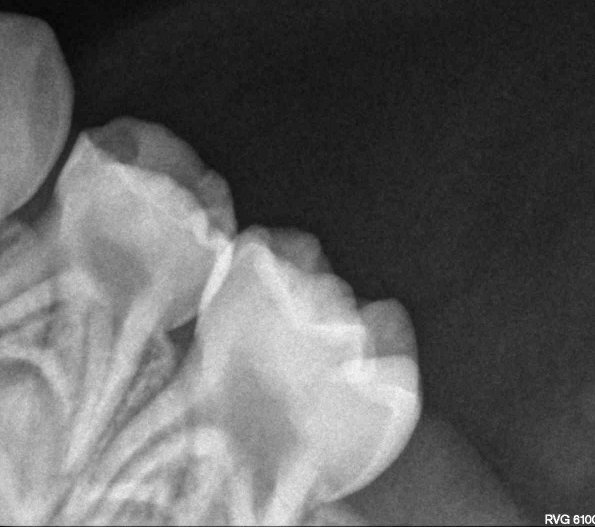

Сложно сказать, к моему большому сожалению, многие врачи забыли о своей заповеди и перешли на абсолютно коммерческую форму лечения. Не надо никому верить, сделайте снимок ОПТГ и выложите сюда.